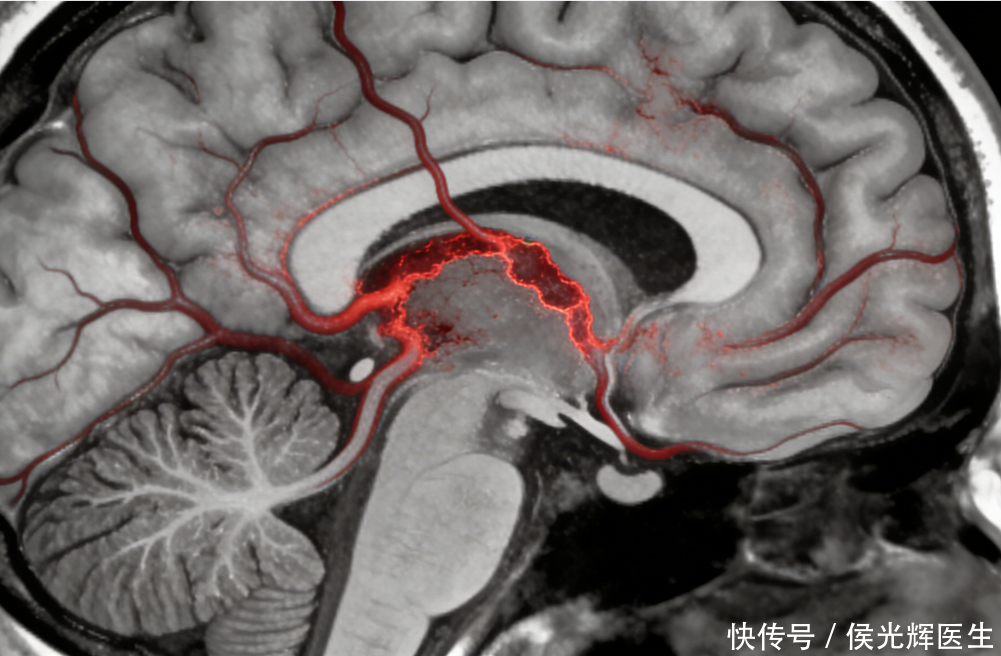

中风,好比大脑里的“电路”突然出现了短路或断电。一部分脑细胞因为缺血缺氧而受损,它们负责的“工作区域”就可能暂时或永久地停工。陈先生所患乃缺血性脑卒中,通俗而言,此病症是脑血管被血栓“阻塞”。血液流通受阻,脑部供血不足,进而引发一系列症状。虽然他现在脱离了生命危险,但受损的神经功能恢复起来,就像修一条被冲垮的道路——需要时间,更需要方法。